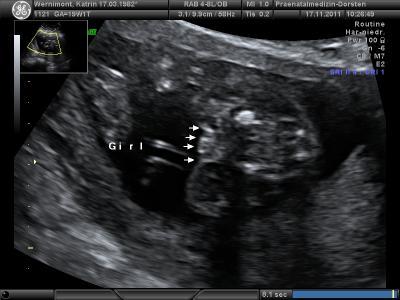

Der FA wo ich heute zur Feindiagnostik war hat mir eben geemailt und 9 weitere Bilder per Email geschickt Oh ich freu mich...Das ist so nett das der das gemacht hat. Den will ich als FA haben! Manno! *hihi* Hier ist das Bild das es ein Mädel ist

Bild zu Awww *freu* - Forum für April - Mamis

Ja, eindeutig....da hängt nichts dran! Find ich ja toll, dass dir der FA die Bilder gemailt hat! Liebe Grüße Sonja

Das ist ja cool von ihm! Stimmt kein schniedel zusehen;) lg

Jepp, das Bild ist wirklich mehr als eindeutig. Da fehlt was zum Jungen Glückwunsch nochmal! LG Jordan